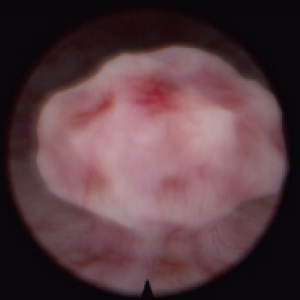

Diagnostic and surgical skills in Hysteroscopy & TUR

Resectoscope for hysteroscopy

Real resectoscope handle. Pedals for coagulation and electric dissection.

Magnetic feedback

Our proprietary magnetic feedback system allows for unprecedented immersion. Furthermore, unlike mechanical feedback systems, it is far more reliable.